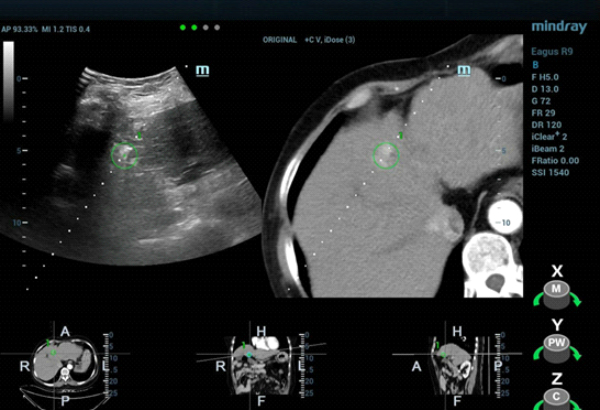

W konwencjonalnym obrazowaniu USG w skali szaro?ci nie uda?o si? uwidoczni? guza w segmencie IV zaobserwowanego w badaniu TK jamy brzusznej. W badaniu USG z kontrastem (contrast-enhanced ultrasound, CEUS) zmiana wykazywa?a wzmo?one unaczynienie w fazie t?tniczej (Obraz 2.) z izointensywnym wzmocnieniem w fazach wrotnej i pó?nej (Obraz 3.)./p>

U pacjentki zaplanowano zabieg ablacji mikrofalowej (microwave ablation, MWA) pod kontrol? USG, jednak z uwagi na fakt, ?e nie uda?o si? uwidoczni? zmiany w konwencjonalnym badaniu USG, w celu zapewnienia dok?adnego pozycjonowania elektrody mikrofalowej wykorzystano obrazowanie metod? fuzji obraz√≥w: ultrasonograficznego i TK z kontrastem (Nagranie 1, Obraz 4вАУ7).

Guz by? izoechogeniczny i nie mo?na by?o wyra?nie uwidoczni? go w badaniu USG 2D w skali szaro?ci, zatem konwencjonalna kontrola wy??cznie z zastosowaniem USG mog?a skutkowa? niedok?adnym pozycjonowaniem i niepe?n? ablacj?. Z kolei obrazowanie z wykorzystaniem fuzji obrazów uzyskanych w badaniu USG w czasie rzeczywistym z danymi uzyskanymi w badaniu TK z kontrastem umo?liwi?o dok?adne pozycjonowanie elektrody i skuteczne leczenie zmiany metod? przezskórnej MWA. Przed zabiegiem przeprowadzono badania CEUS w celu potwierdzenia umiejscowienia guza oraz po zabiegu w celu oceny obszaru poddanego ablacji i potwierdzenia skuteczno?ci leczenia.